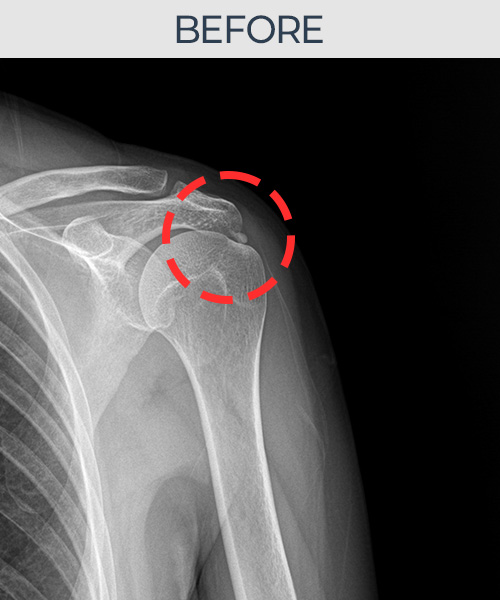

수천건의 수술 경험을 바탕으로 정확히 진단하여

인대파열을 비수술로 치료합니다.

플래티넘정형외과에서는 수술이 필요없는 인대파열만을

정확히 진단하여 특허받은 술기로 비수술로 치료합니다.